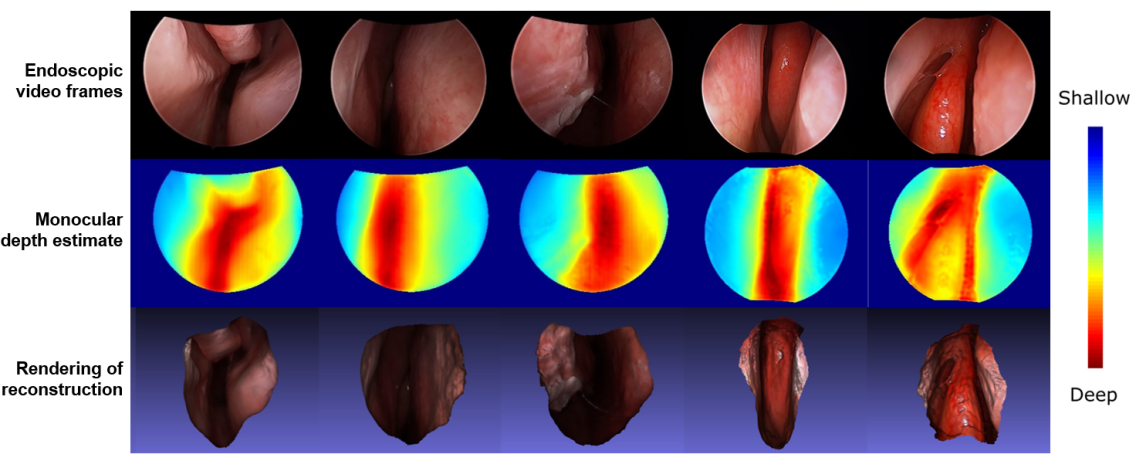

V-C Reconstructing Anatomic Geometry